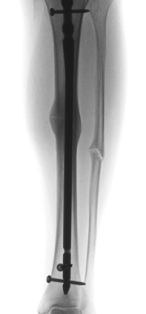

Abbildung 2: Stabilisierung mit einem Marknagel (UTN). Vollständige Wiederausrichtung der anatomischen Verhältnisse.